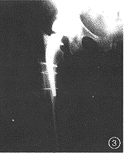

例3女,68岁,右侧人工股骨头置换术。术后当天发现股骨近端骨折,假体远端从内侧皮质穿出,再次进行内固定术。术后右侧髋关节负重即出现疼痛,X线片示假体外翻位,假体柄自内侧骨皮质穿出(图3)。

图1男,72岁,右全髋关节置换术后5年。右股骨假体内翻下沉,假体远端骨水泥断裂,髋臼假体周围有连续的透亮区图2女,65岁,人工股骨头置换术后5年。髋臼内壁磨损,容积性骨缺损图3女,68岁,右侧人工股骨头置换术。假体外翻位,假体柄自内侧骨皮质穿出图4男,40岁,股骨颈骨折后股骨头缺血性坏死。行人工股骨头置换术,人工股骨头过度前倾位置入图5男,67岁,左侧全髋关节置换术后7年。假体股骨柄断裂,股骨假体近端内翻,骨水泥周围透亮区形成图6男,62岁,左侧全髋关节置换术后4年。髋臼假体金属杯与聚乙烯内衬脱位,髋臼金属假体与股骨假体直接接触